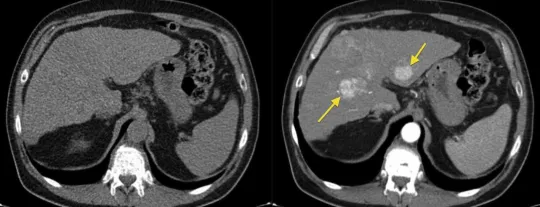

Использование контрастного вещества в компьютерной томографии существенно изменяет качество получаемых изображений. Ниже представлены основные различия между КТ с контрастом и без него:

- КТ с контрастом позволяет лучше выделять мягкие ткани, сосуды и новообразования.

- Без контраста может быть сложно различить похожие на первый взгляд структуры.

Качество снимков:

- Снимки, сделанные с использованием контраста, имеют более высокую четкость и контрастность.

- КТ без контраста может показывать размытые или непробиваемые участки, затрудняя интерпретацию.